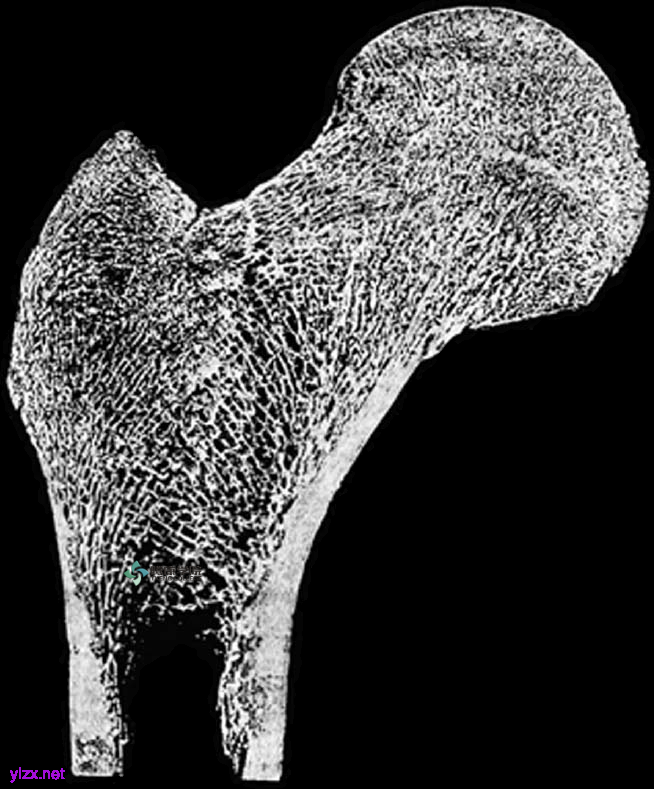

中空骨骼内的格子状骨小梁所承受的压力和拉力的方向。

骨矿化胶原纤维的符合纳米结构可避免微小的骨骼分离,并为骨骼增加惊人的弹性。像合成纤维/基质纳米符合材料一样,它非常坚固,也能承重,甚至比水泥更强。

在结构上,这些磷灰石晶体本身相对较弱,就像是粉笔一样。然而,在体内,这些矿物纳米晶体与薄的柔性胶原纤维两种分子连接并交织,形成类似玻璃或竹子的纤维/基质复合材料。

在骨骼中,这种基质占骨骼重量的一半,其在微观结构中主要由磷酸盐和钙组成,称为羟基磷灰石。